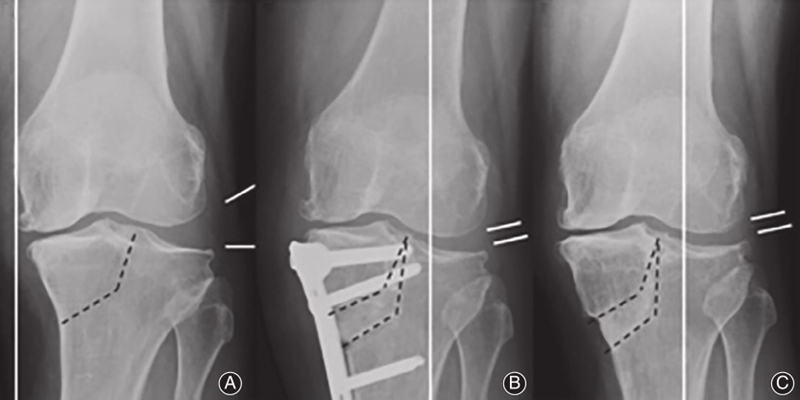

图1

传统的HTO技术无法对关节内畸形进行矫正,因此在合并外侧半脱位的重度膝关节骨关节炎病例中往往难以达到满意的治疗效果。Chiba[9]基于传统HTO技术所面临的困境,于1992年提出了胫骨髁外翻截骨术(tibial condylar valgus osteotomy,TCVO)。TCVO为开放性楔形HTO的一种,由胫骨近端内侧向髁间隆起行"L"形截骨,旨在矫正膝内翻、外移下肢力线的同时修复半脱位的外侧膝关节。日本学者Teramoto T[10]等认为TCVO适用于所有年龄、所有等级的膝内翻OA患者。TCVO的基本原则是通过关节内畸形的关节内矫正来稳定膝关节。这种关节内截骨术改善了骨性和软组织的不稳定性,不需要单独的韧带重建。临床结果证实经tvo治疗后,患者疼痛得到改善,能够恢复繁重的体力劳动和运动活动。国内学者王峰、康庆林团队[11]对接受TCVO手术的内翻型单间室膝关节骨关节炎患者32例(45膝)进行回顾性分析,发现TCVO治疗膝关节外侧间隙增宽、关节线会聚角增大的内翻型单间室膝关节骨关节炎可以取得良好的早期疗效,有效矫正膝关节内翻畸形并外移下肢机械力线,缓解术后早期膝关节疼痛及改善日常活动能力。